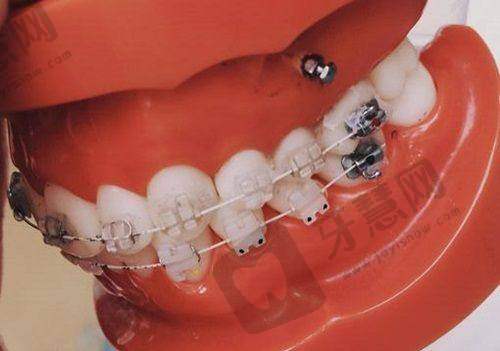

2. 正畸项目:结合数字化方案设计,能更好地平衡咬合功能与美学。陈春美医生擅长隐形矫正,拥有超500例隐形矫正实例,可根据患者具体情况制定个性化方案。

2. 陈春美医生:专注正畸领域,隐形矫正库超500例。擅长结合数字化方案设计咬合功能与美学平衡,能根据患者不同情况制定个性化矫正方案,为患者提供优质的正畸服务。

2. 牙齿矫正项目:我牙齿不齐,影响美观。陈春美医生为我制定了隐形矫正方案。矫正过程中,陈医生经常和我沟通,及时调整方案。现在我的牙齿变得整齐了,而且矫正过程特别舒适,没有什么不适感,真的特别满意。